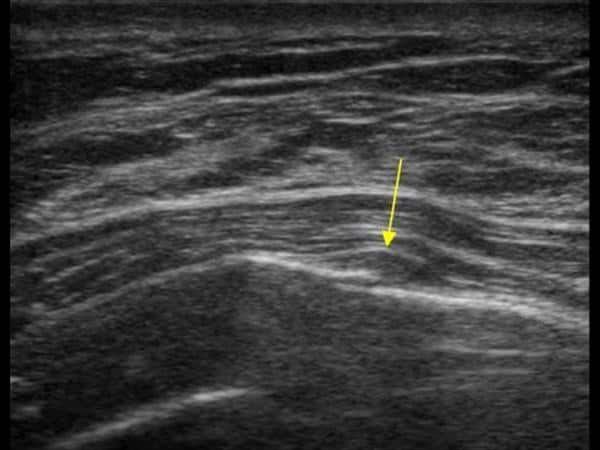

Gãy xương sườn

Gãy xương sườn - Ảnh 4

» Thông tin: Nữ giới – 52 tuổi.

» Lâm sàng: Chấn thương ngực.